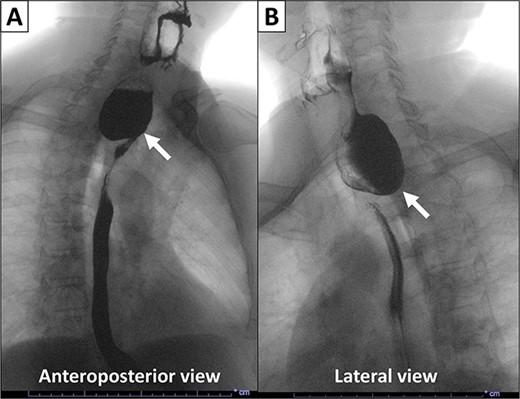

This is a case of a 74-year-old man with a history of diabetes mellitus and hyperlipidemia, who presented to our institution with chronic regurgitation, dysphagia and halitosis. The patient was initially seen in 2015 at which point he reported a 10-year history of these symptoms and was diagnosed with ZD (Fig. 1). He had frequent chocking and aspiration events and worsening symptoms in the past few months. Surgical history included cholecystectomy in 2010 and partial gastrectomy in 1989 for stomach cancer. Vital signs on admission were normal. His body mass index was 26.71 kg/m2. Physical examination and laboratory values on admission were normal. The patient never smoked and does not drink alcohol.

X-ray esophagogram performed in 2015. Esophagogram with barium suspension showed a 4 × 5 cm Zenker’s diverticulum with a 1.7 cm wide diverticular neck.